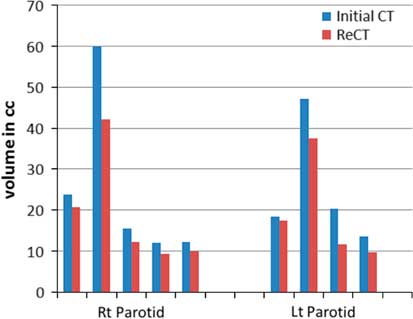

Re-scanning and re-planning at 20th fraction of the treatment shows 27% (13–42%) reduction in parotid volumes (Figure 2), and therefore 21% (7–35%) increase in parotid mean doses. Initial plan calculated on ReCT and CBCT found 15% (9–26%) increase in planning risk volume (PRV) spine maximum doses, which were reduced by re-planning on ReCT. The body maximum doses increased by 6·5% (4–8%) in four patients and 22% in one patient when initial CT plan was calculated on ReCT and CBCT. These results showed a statistically significant difference in the parotids, PRV spine and skin doses with a p-value of 0·01, 0·007 and 0·02, respectively. Figure 3 is the graphical representation of mean doses of parotids and maximum doses of PRV spine and skin in all three plans (initial CT plan, initial plan calculated on ReCT and CBCT).

Figure 2 Parotid volume graphs from initial CT to ReCT in all five patients.